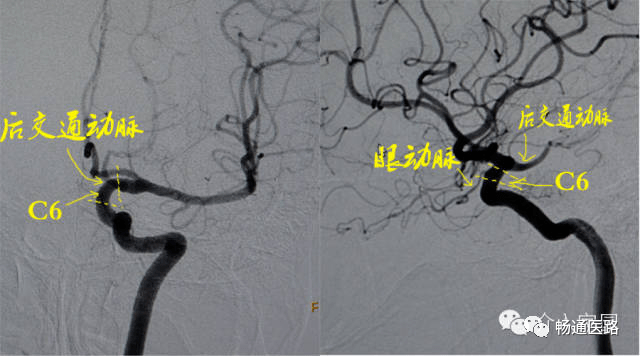

颈内动脉c6段在侧位脑血管造影显示最清楚, 在与c5段(床突段)交界处远